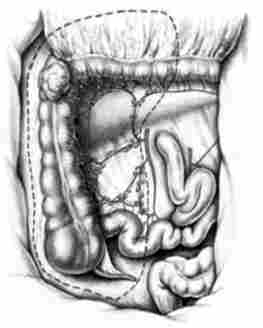

Лівостороння геміколектомія (рис. 14.10) виконується при локалізації пухлини в селезінковому вигині, в низхідному відділі і проксимальної частини сигмовидної кишки. Нижня брижова артерія часто зберігається (не перетинається), а з даного басейну лігуються ліві ободової судини. Одночасно видаляється заочеревинна клітковина з лімфатичними вузлами. Операція закінчується формуванням трансверзосігмоідного анастомозу (анастомозу між поперечної ободової кишкою і сигмовидної кишкою).

Сегментарна резекція виконується при пухлинах середньої третини поперечної ободової кишки і сигмоподібної кишки. Разом з ділянкою кишки проводиться клиновидное висічення брижі (рис. 14.11).

У разі розвитку первинно-множинного раку ободової кишки виконують субтотальную колекгомію з формуванням илеоректального анастомозу (рис. 14.12).

лівостороння геміколектомія

Мал. 14.10. лівостороння геміколектомія

Рсзсцкія кишки

Мал. 14.11. Рсзсцкія кишки:

а - поперечної ободової; б - сигмовидної

субтотальна колектомія

Мал. 14.12. субтотальна колектомія